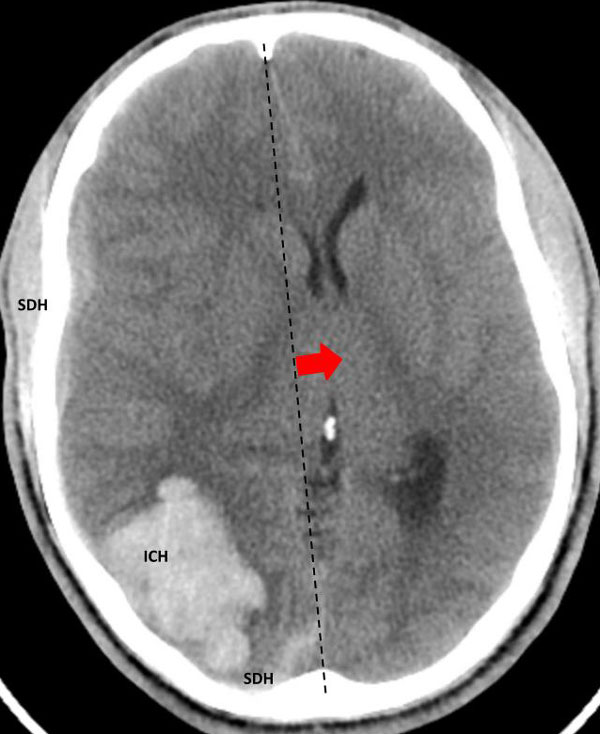

Fig 1. Head CT scan showing large right-sided, parieto-occipital intra-cerebral hemorrhage (ICH) and small occipital and temporal subdural hemorrhage (SDH) with right to left midline shift (red arrow).

A head CT revealed a large posterior-parietal intracerebral bleed, an acute subdural clot, and right to left midline shift (Fig 1). Following the review of a head CTA, the patient was diagnosed with a ruptured brain arteriovenous malformation (AVM). Urgent treatment was indicated for this acute intracerebral hemorrhage (ICH) with significant mass effect and the risk of catastrophic rebleeding of the AVM.